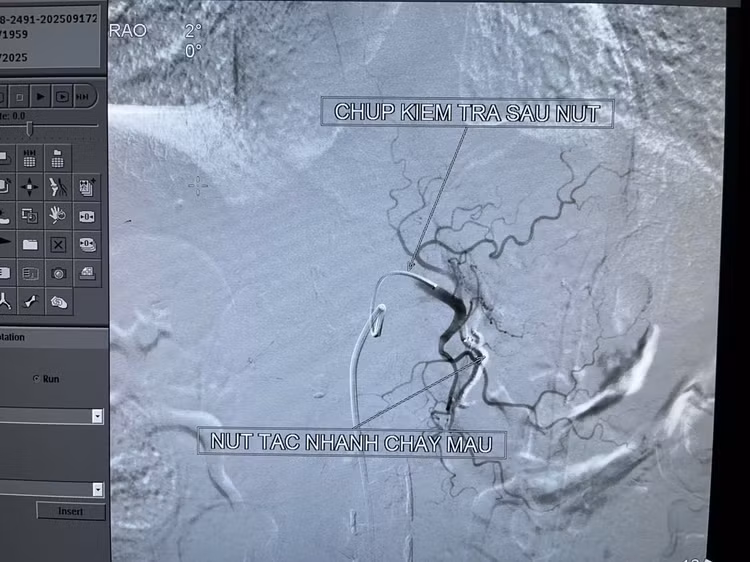

Qua chụp CT tiêm thuốc cản quang và chụp mạch trên máy DSA, thấy được vị trí chảy máu dạ dày tương đối lớn. Các bác sĩ đã tiến hành nút tắc toàn bộ nhánh động mạch chảy máu. Sau can thiệp, chụp kiểm tra lại, hệ thống động mạch không còn điểm chảy máu nào khác trong ống tiêu hóa.

Kỹ thuật nút mạch cầm máu chảy máu tiêu hóa cao cũng như xuất huyết các tạng trong ổ bụng là kỹ thuật tiên tiến nhất, can thiệp tối thiểu và đạt hiệu quả tối đa.